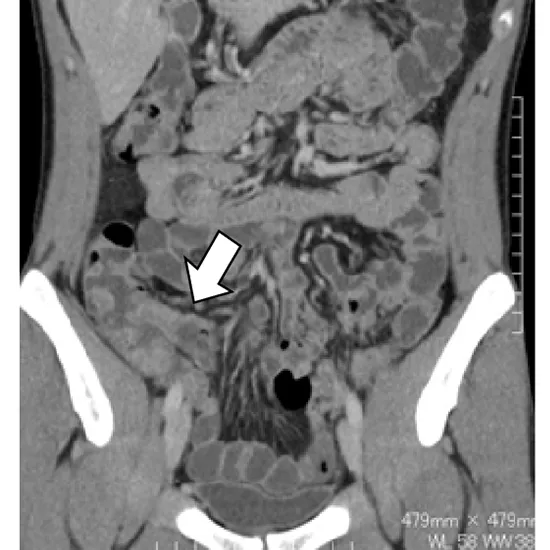

CT enterography is an imaging test that examines the small intestine using CT imagery and a contrast material. The procedure enables your doctor to determine what is causing your condition. He or she can also tell you how well you're responding to treatment for a medical condition like Crohn's disease.

CT enterography produces detailed images of the small intestine and structures within the abdomen and pelvis by using special x-ray equipment and an injection of contrast material after the ingestion of liquid. It is frequently used to identify and locate bowel problems such as inflammation, bleeding, obstructions, and Crohn's disease. CT scanning is quick, painless, non-invasive, and precise. When compared to other small intestine imaging procedures, CT enterography can visualise the entire thickness of the bowel wall.